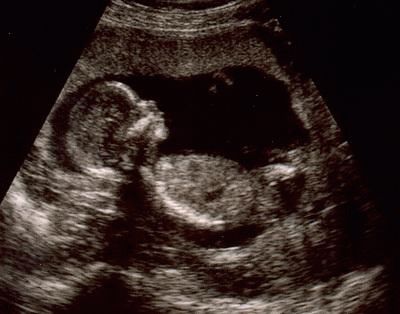

Selon votre état et votre bien-être, des tests généraux et des échographies peuvent être prescrits. Pendant l'analyse, le médecin vérifiera la quantité de liquide amniotique, la position du placenta. De plus, les principaux indicateurs du fœtus (tailles privées et générales, fréquence cardiaque, etc.). Si vous connaissez encore le sexe de votre enfant, avec la localisation réussie du bébé, le spécialiste pourra vous révéler ce secret.